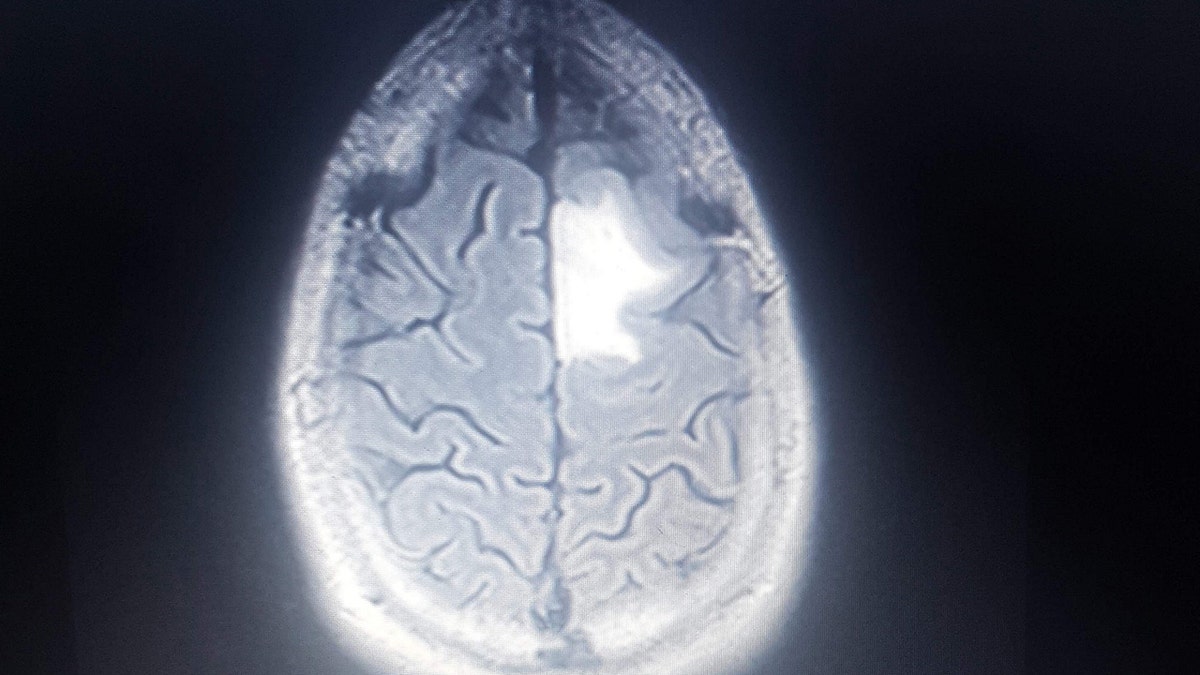

"I had multiple scans at the hospital in Orlando," he said. "As the results came back it was the last thing I thought the doctor would say, ‘Mr Reid, the MRI scan has shown a frontal lobe brain tumor in the front left of your brain.' This is the point my life changed."

Just two weeks later, Reid was facing an awake craniotomy brain tumor surgery to remove as much of the 3.5-cm mass as possible.

Doctors discovered after the surgery that Reid’s tumor had grown from a grade two to grade three tumor -- cancer cells appear distinctly abnormal under the microscope.